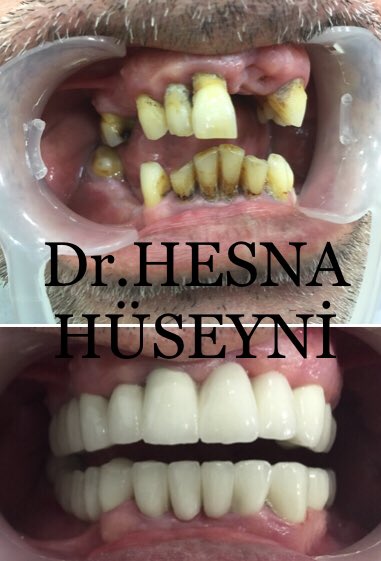

Dr.Hesna Huseyni

@hesnahuseyni

#prosthodontist

#dentist